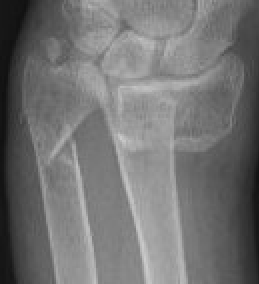

Classification ulna styloid fractures

| Type 1: Tip | Type 2: Base | Type 3: Proximal to styloid |